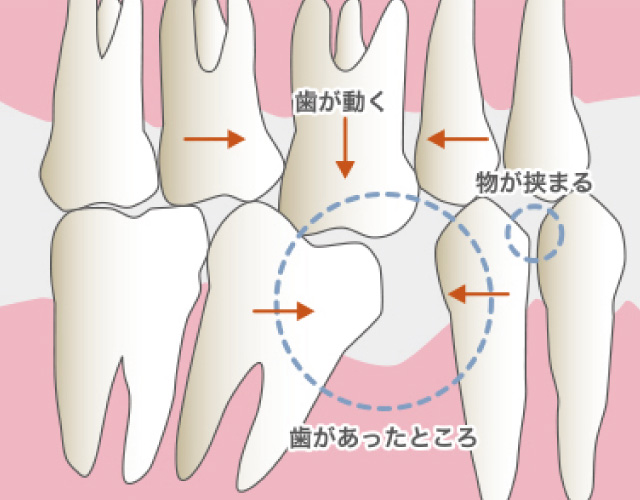

一度歯を失ってしまうと、天然の歯は二度と元に戻ることはありません。その失われた歯が引き金になり、隣の歯がドミノ倒し的に悪化してしまう可能性もあります。しかし、インプラント治療を行うことで、自分の歯とほとんど変わらない見た目や、噛み心地を得ることが出来ます。ご自身の健康な歯を守ることができます。